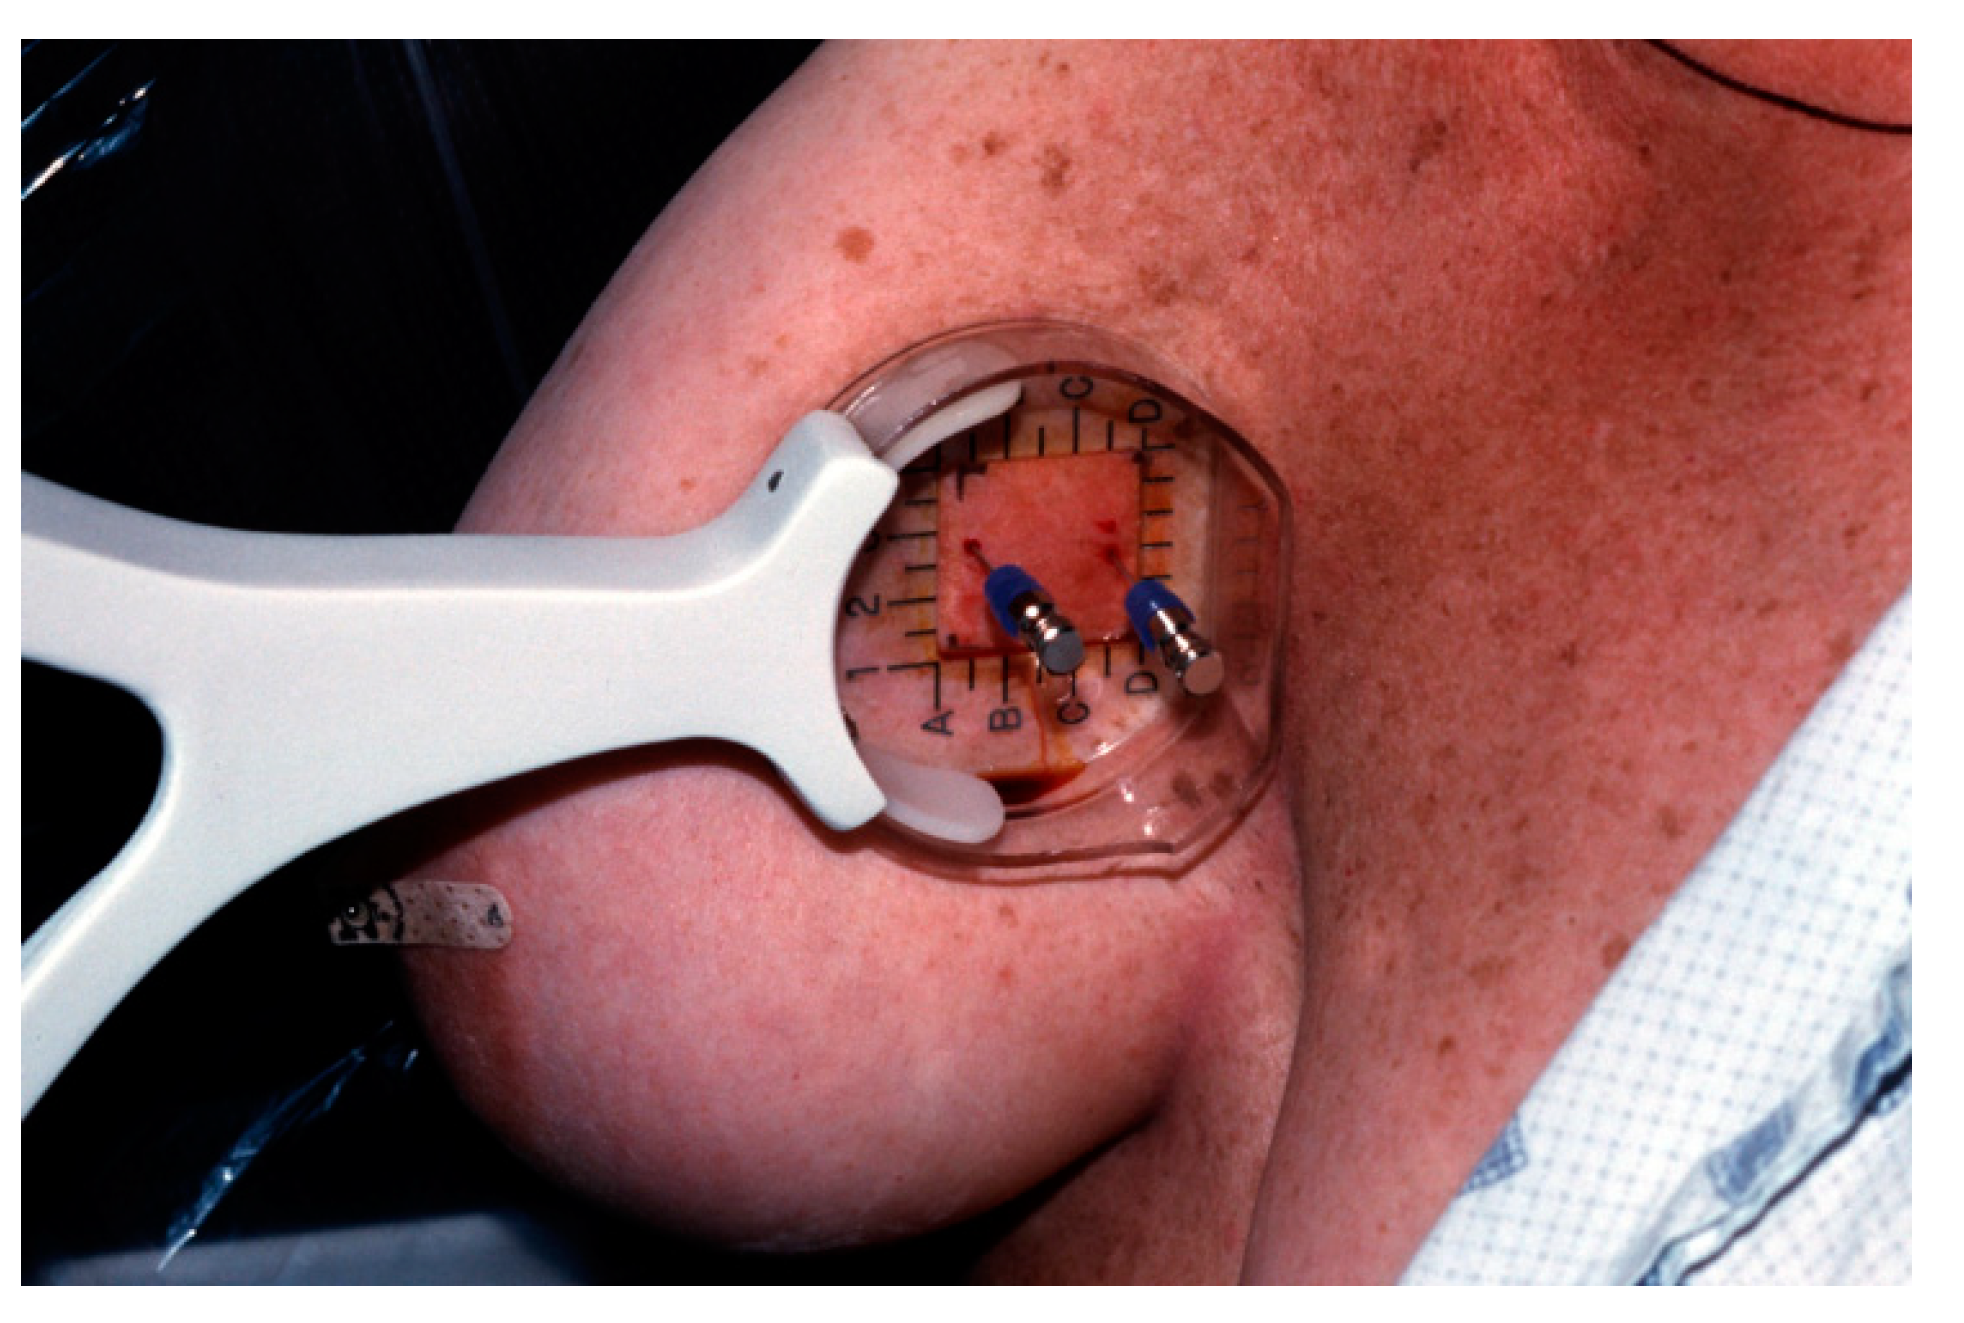

Two tuberculin syringes are added to the standard procedure tray (Figure 4) for mammographically-guided SLNB. The radiopharmaceutical is kept in a lead container until the time of injection. Four mL of Tc-99m-sulfur colloid is injected in divided doses through the localizing needles (Figure 5). Hawkins, Homer, spinal (Figure 6) and Kopans needles have been used for mammographically–guided SLNB. After the injection of Tc-99m-sulfur colloid, saline is injected through tuberculin syringes to flush the localization needles (Figure 7).

Figure 4. Procedure tray for mammographically-guided SLNB with two tuberculin syringes (arrows).